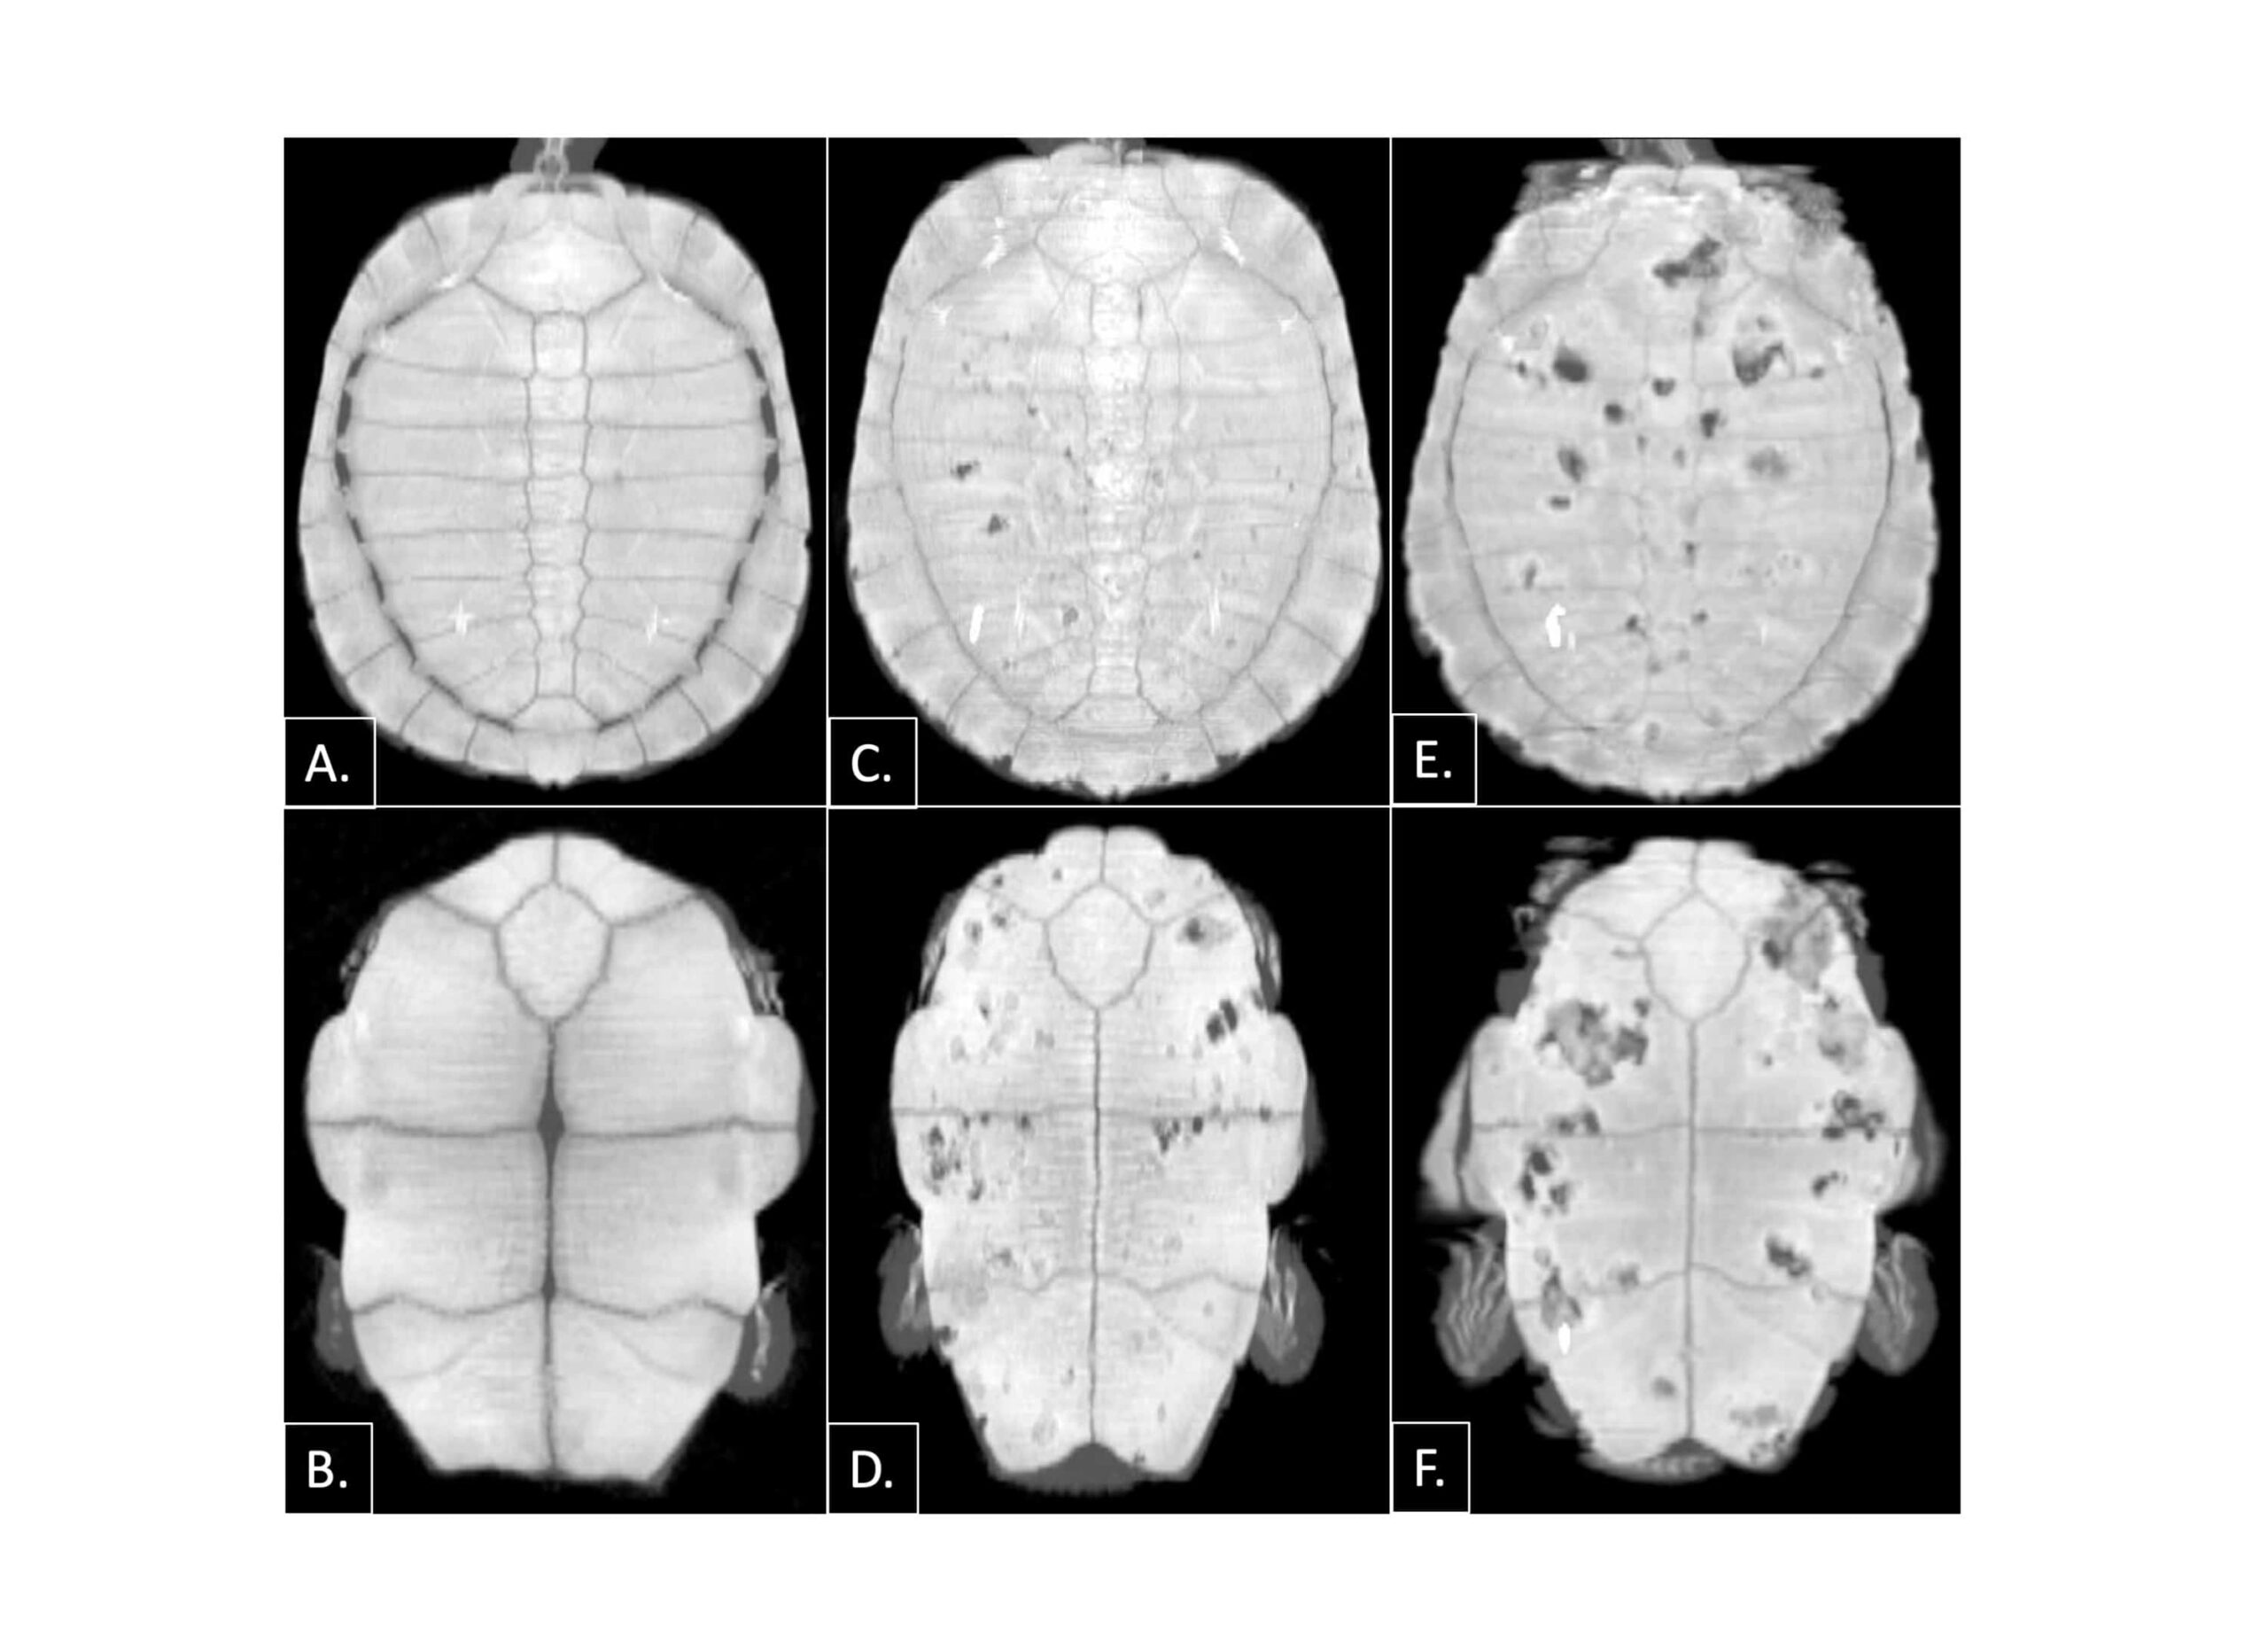

Without CT scans it’s hard to tell if the turtles have the shell disease until they’ve been afflicted for some time. The turtles may appear outwardly healthy, but CT scan can show severe lesions.

The prevalence of the disease is quite high among the turtles they head-start: Between 65% and 85% of Washington’s western pond turtles have shell disease, based on CT scans.